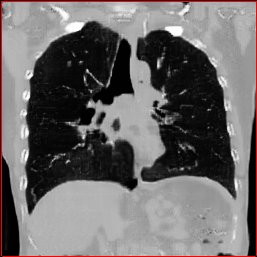

HA-GAN (Sun et al. 2022)

GenerateCT (Hamamci et al. 2024)

MedSyn (Xu et al. 2024)

MAISI-DDPM (Guo et al. 2025)

MAISI-v2

Figure 2: Qualitative comparison across axial (top row), sagittal (middle row), and coronal (bottom row) views. Columns correspond to different methods. MAISI-DDPM and MAISI-v2 in this figure are unconditional synthesis which do not use ControlNet or segmentation maps.

Qualitative Evaluation:

Figure 2 presents representative slices from the axial, sagittal, and coronal planes. GenerateCT (Hamamci et al. 2024) is a 2D model, so it lacks inter-slice consistency, leading to poor image quality in the sagittal and coronal views. MedSyn (Xu et al. 2024) produces noticeably blurry results with mosaic-like artifacts, such as region inside the red box. HA-GAN (Sun et al. 2022) generates visually sharp images but with mosaic-like artifacts, such as region inside the red box. Also, its voxel spacing is not available, which limits its applicability in real-world medical imaging tasks. Moreover, all three methods are restricted to synthesizing small anatomical regions. In contrast, both MAISI and MAISI-v2 are capable of generating high-quality 3D volumes that span larger body regions while preserving fine anatomical details and realistic structure.